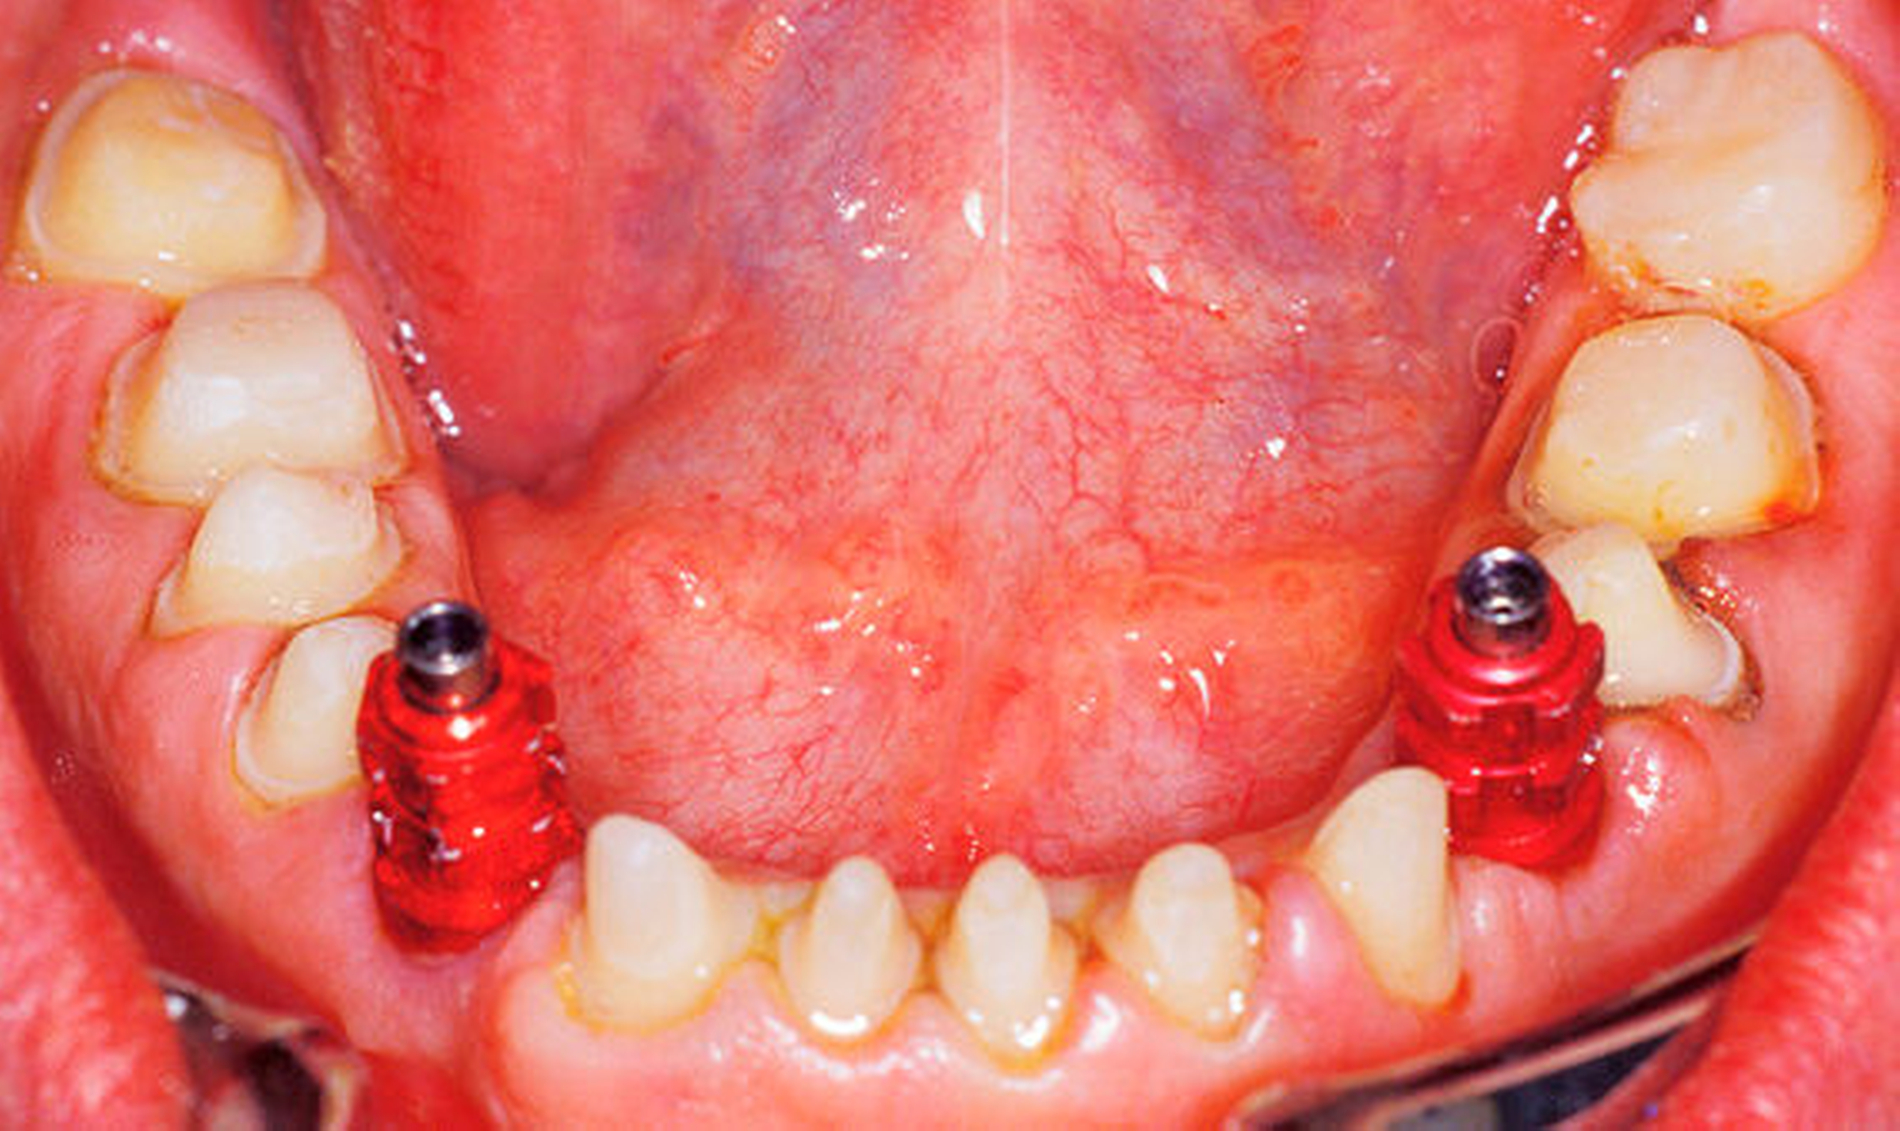

Nach viermonatiger Einheilzeit des letzten Implantats erfolgte nach diagnostischem Aufwachsen die Präparation und Abformung des Großteils der Zähne im Ober- und im Unterkiefer zugleich mit der offenen Abformung der Implantate (Abbildung 9). (Zur Erleichterung der Bissnahme wurden vorerst einige Molaren belassen und erst in einer zweiten Etappe beschliffen und versorgt.) Nach Montage der Modelle wurden Lithiumdisilikat-Restaurationen für die natürlichen Zähne und verblendete Zirkonoxidkronen auf konfektionierten, individualisierten Titanabutments (Abbildung 10) hergestellt. Nach einer Einprobe wurden die Kronen auf den Zähnen adhäsiv, die Implantatkronen konventionell mit einem Zinkoxidphosphat-Zement eingesetzt. Die Behandlung der restlichen Zähne wurde in analoger Weise durchgeführt.